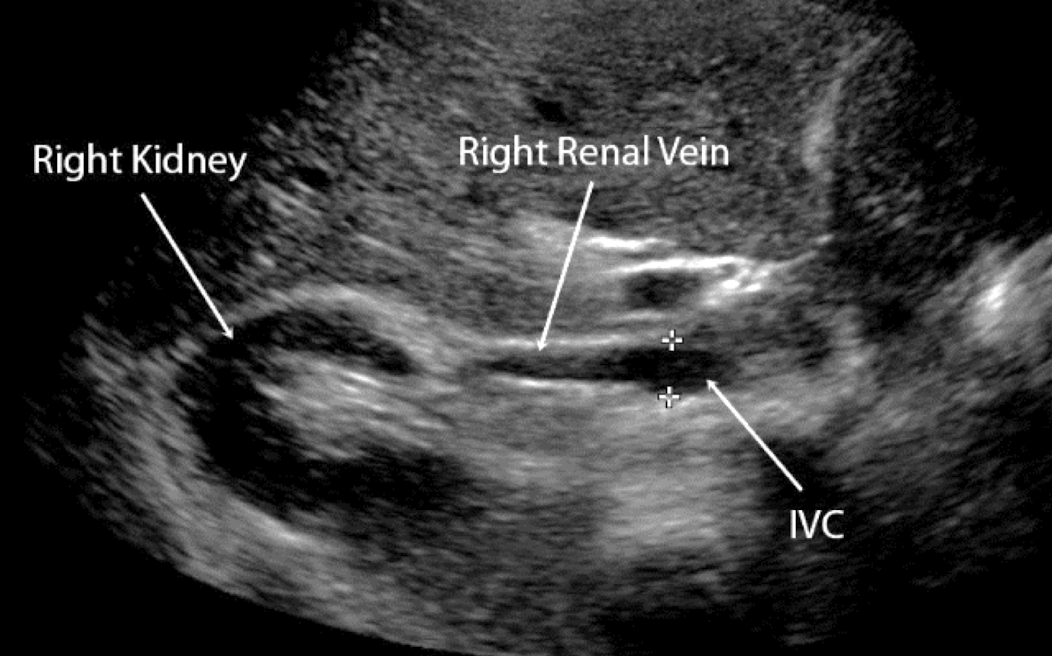

what is the course of the RRV?

RRV extends from central renal sinus directly into IVC